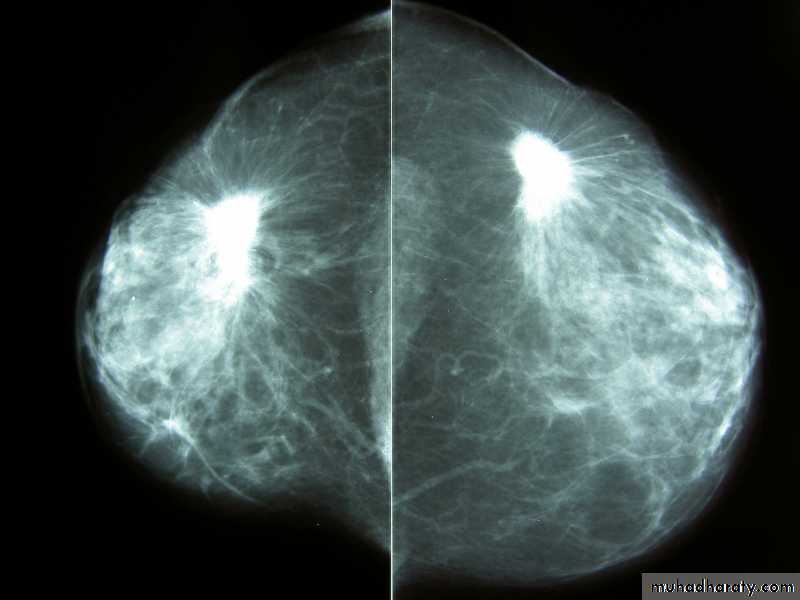

male &female reproductive tractsmammogram

Benign calcification

Malignant microcalcification